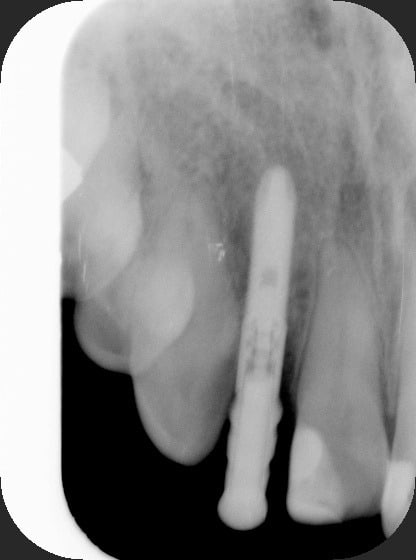

après beaucoup de temps de réflexion...nous avons décidé de garder l'implant tel quel...je vous envoie les photos, vous comprendrez....

Conclusion: il était pas si mal placé cet implant !

> Conclusion: il était pas si mal placé cet implant !

en fait l'inclinaison n'est pas top mais la situation n'est pas si mauvaise...

les diastèmes lui vont pas si mal à ma patiente...c'est vrai que les modèles et les radios font peur, mais une fois qu'on l'a en face, on change un peu d'avis....non?

Scelle avec du ciment mou, un hexagone Branemark avec un tel bras de levier ça va se dévisser, ce schbynze.